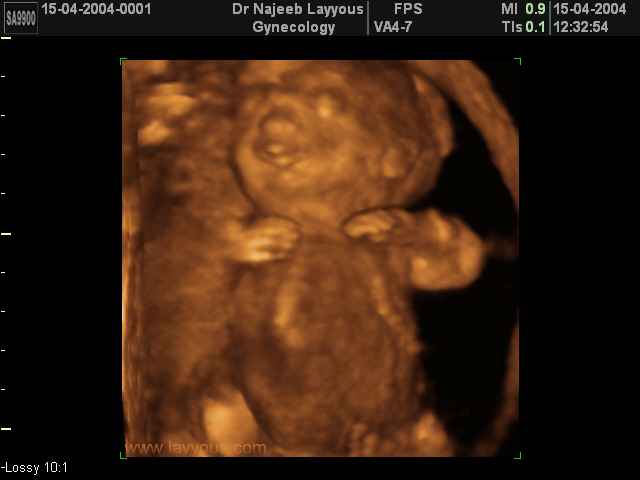

- لقطات فيديو للجنين بجهاز الموجات فوق صوتية رباعي الأبعاد

- صور لوجه الجنين في داخل الرحم

- صور لأعضاء الجنين

- صور لأطراف الجنين

- صور لتصرفات الجنين داخل الرحم

- صور للجنين في المراحل المتوسطة من الحمل